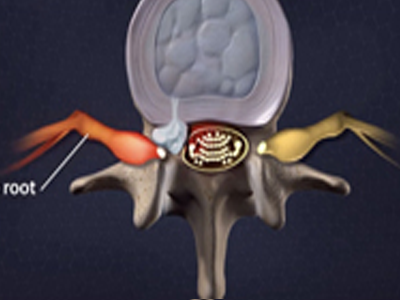

脊柱脊髓神经微创中心以微创技术为引领,以功能恢复为目标,主要治疗脊柱外伤、肿瘤、退行性病变、脊柱畸形等疾病。团队利用神经外科显微技术,结合神经内镜微创技术,对脊柱间盘变性疾病、颈腰椎管狭窄、颈腰椎间孔狭窄、颈腰椎间盘突出、颈腰椎体不稳、脊柱骨折、寰枢椎脱位、脊柱肿瘤、椎管内肿瘤、脊髓损伤、脊髓空洞、脊髓栓系等疾病进行高效、特色手术治疗,如颅颈交界区畸形寰枕减压内固定术、脊柱肿瘤全脊椎切除内固定术、微创椎管内肿瘤切除术、微创脊柱旁肿瘤切除术、寰枢椎脱位椎间融合内固定术、脊柱骨折微创经皮椎弓根钉内固定术、经椎间孔椎间融合内固定术(MIS—TLIF)等,最大程度降低脊柱脊髓手术创伤,具有创伤小、输血少、恢复快、口碑好,出院早等优势。

• 1椎管扩大成形术

• 2脊柱肿瘤全脊椎切除内固定术

• 3微创椎管内肿物切除术

• 寰枢椎脱位椎间融合内固定术 4

• 5脊柱骨折+腰椎滑脱-椎弓根钉内固定术

• 颈椎间盘切除、椎管减压术 6